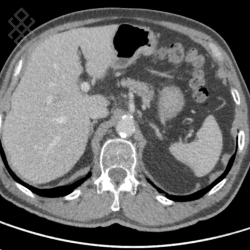

Scanner Thoraco-abdomino-pelvien